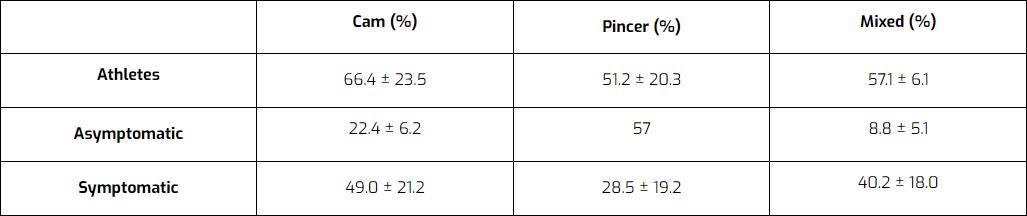

Es wird angenommen, dass sich diese Morphologie als spezifische Anpassung an die Anforderungen während der Adoleszenz entwickelt. Es könnte sein, dass sich die Wachstumsplatte verschiebt, wodurch der Kopf weniger rund, aber größer wird. Sobald sich die Wachstumsfugen schließen, ändert sich die Morphologie nicht mehr. Die Morphologie des FAI ist bei asymptomatischen Menschen und sogar bei 50-70 % der Sportler häufig. Viele Menschen haben also Anomalien, aber nur ein kleiner Teil entwickelt Schmerzen.

Ein Bericht von Mascarenhas et al. (2016 ) listet den prozentualen Anteil von Patienten mit Cam-, Pincer- oder Mischmorphologie-FAI in sportlichen, asymptomatischen und symptomatischen Populationen auf. Die Ergebnisse: